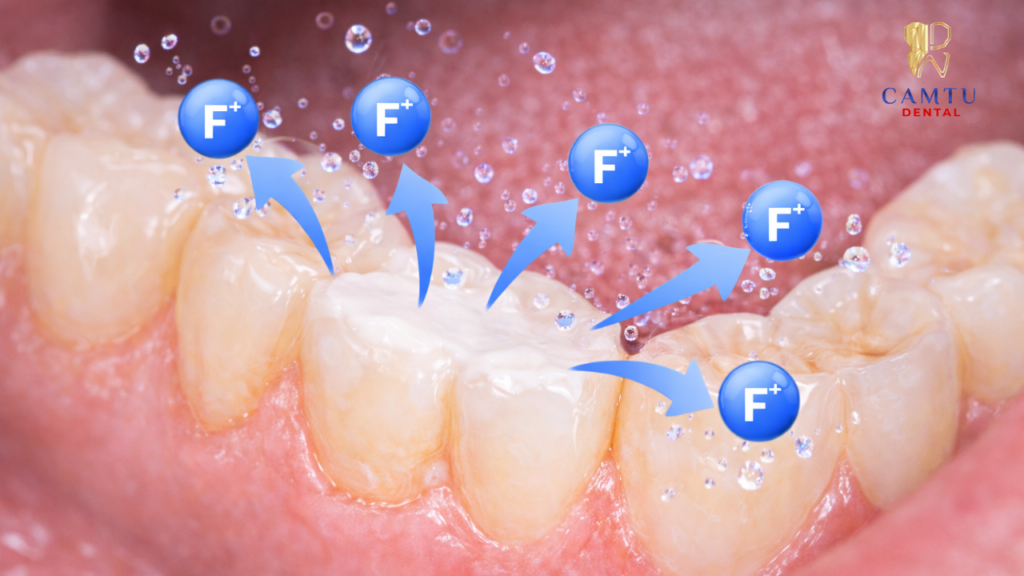

Một trong những điểm nổi bật của vật liệu GIC là khả năng giải phóng fluoride. Fluoride giúp tái khoáng men răng và hỗ trợ phòng ngừa sâu răng tái phát. Vì vậy, phương pháp này được đánh giá là khá an toàn và có lợi cho sức khỏe răng miệng.

Fluoride được giải phóng từ vật liệu trám có tác dụng hỗ trợ tăng cường men răng và giúp giảm nguy cơ sâu răng tái phát. Điều này đặc biệt quan trọng đối với trẻ nhỏ, khi răng sữa vẫn cần duy trì khỏe mạnh để đảm bảo chức năng ăn nhai và định hướng cho răng vĩnh viễn mọc đúng vị trí.

Một trong những ưu điểm nổi bật của vật liệu Glass Ionomer là khả năng giải phóng fluoride trong quá trình tồn tại trên răng. Fluoride có vai trò quan trọng trong việc tăng cường độ cứng của men răng và hỗ trợ quá trình tái khoáng tự nhiên.

Nhờ đặc tính này, trám răng GIC không chỉ giúp phục hồi phần răng bị tổn thương mà còn góp phần giảm nguy cơ sâu răng tái phát, từ đó hỗ trợ bảo vệ răng miệng lâu dài.

Trám răng GIC có phòng ngừa sâu răng không?

Có. Vật liệu Glass Ionomer có khả năng giải phóng fluoride giúp tăng cường men răng và hỗ trợ phòng ngừa sâu răng tái phát.